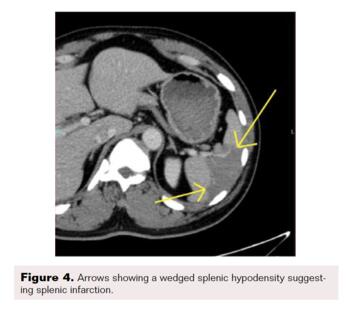

A contrast-enhanced CT scan was completed and revealed stenosis of the celiac trunk and mild bulbous dilatation of the post-stenotic celiac trunk (Figure 1). There was the appearance of a dissection flap that developed into an eccentric hypodense non-enhancing false lumen. This appeared to extend into the common hepatic arterial trunk and the splenic arterial branch, then continued to the splenic hilum (Figure 2 and Figure 3). In addition, there was a large splenic hypo-density involving almost one-third of the central spleen (Figure 4). The findings were consistent with an acute dissection of the splenic and hepatic arteries, along with splenic infarction of the central one-third of the spleen. A differential diagnosis of arcuate ligament syndrome was also considered, given the significant scoliosis seen on scout film of the CT scan (Figure 5).